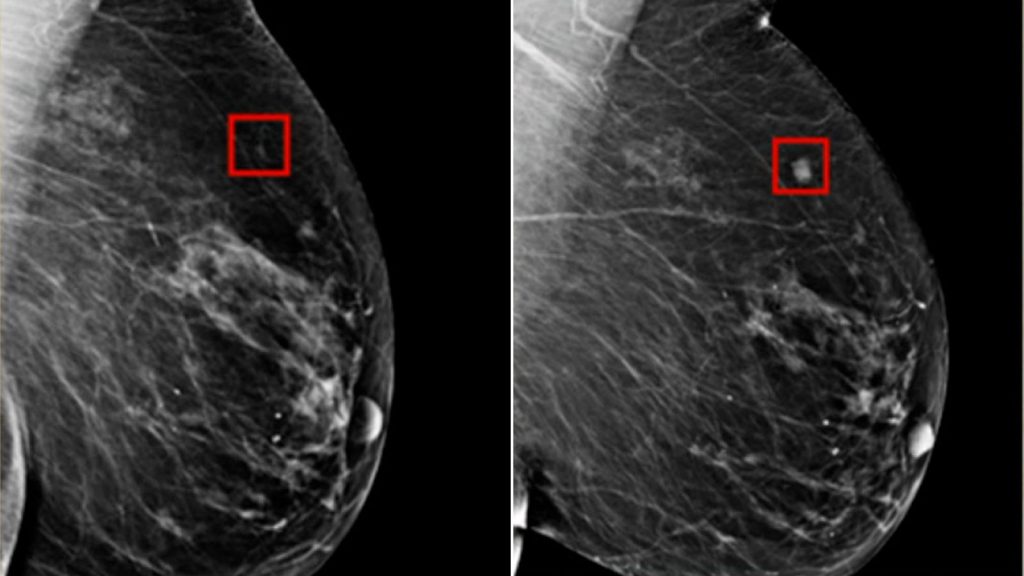

• AI sẽ giúp bác sĩ chẩn đoán bệnh sớm hơn qua phân tích hình ảnh y khoa hoặc xét nghiệm gen.

🏥 Ví dụ: Các bệnh viện hiện nay đã dùng AI để phát hiện ung thư vú, phổi với độ chính xác cao hơn cả bác sĩ.

Xu hướng công nghệ AI - Phát hiện sớm ung thư

Hình ảnh cho thấy AI phát hiện ung thư vú 4 năm trước khi nó phát triển (Nguồn: CNN)